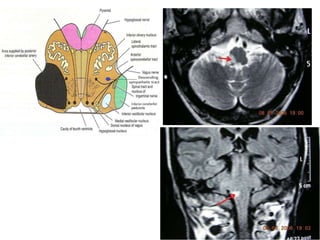

Medulla

Lateral medullary syndrome

(Wallenberg Syndrome – PICA occlusion)

A. IPSILATERAL

1.Xth cranial nerve palsy

2.Cerebellar signs

3.Horner’s syndrome

4.Impaired pain, temperature

and touch on the upper

half of face

B. CONTRA LATERAL

Medial medullary syndrome –

Anterior Spinal Artery occlusion

A.IPSILATERAL

1.XIIth nerve palsy

B.CONTRALATERAL

1.Hemiplegia – sparing the

face

2.Hemianaesthesia sparing the

face.